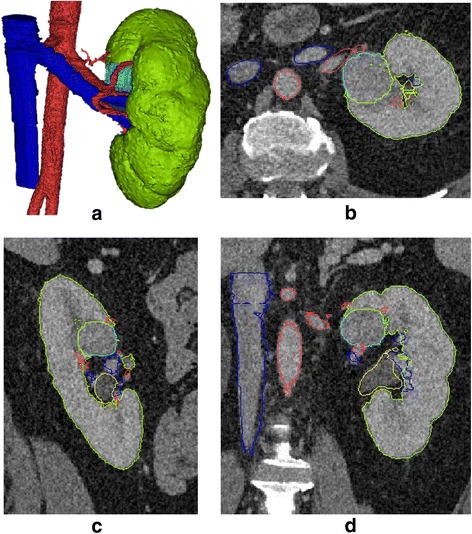

It is essential to check for accuracy of the segmentation and processing as the last step before printing. This can be achieved by overlaying the final STL files on top of the original source images (Fig. 6). Users should inspect the entire image set in all three (axial, coronal and sagittal) planes as errors may be more obvious in one plane than the other. This is especially important if the segmentation process is performed primarily in one plane (e.g. axial). Final approval from the radiologist should be obtained before sending the model to the printer.

Fig. 6.

A renal mass model (a) with segmented results overlaid on original images in axial (b), sagittal (c) and coronal (d) planes. Different colors indicate different segmented objects